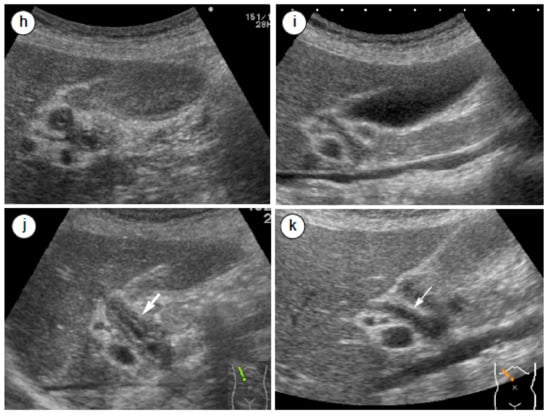

4.3. Radiological and Ultrasonographic Evaluation for Assessing AIP Response to Steroids

- Matsubayashi, H.; Yoneyama, M.; Nanri, K.; Sugimoto, S.; Shinjo, K.; Kakushima, N.; Tanaka, M.; Ito, S.; Takao, M.; Ono, H. Determination of steroid response by abdominal ultrasound in cases with autoimmune pancreatitis. Dig. Liver Dis. 2013, 45, 1034–1040. [Google Scholar] [CrossRef]

- Okabe, Y.; Ishida, Y.; Kaji, R.; Sugiyama, G.; Yasumoto, M.; Naito, Y.; Toyonaga, A.; Tsuruta, O.; Sata, M. Endoscopic ultrasonographic study of autoimmune pancreatitis and the effect of steroid therapy. J. Hepatobiliary Pancreat. Sci. 2012, 19, 266–273. [Google Scholar] [PubMed]